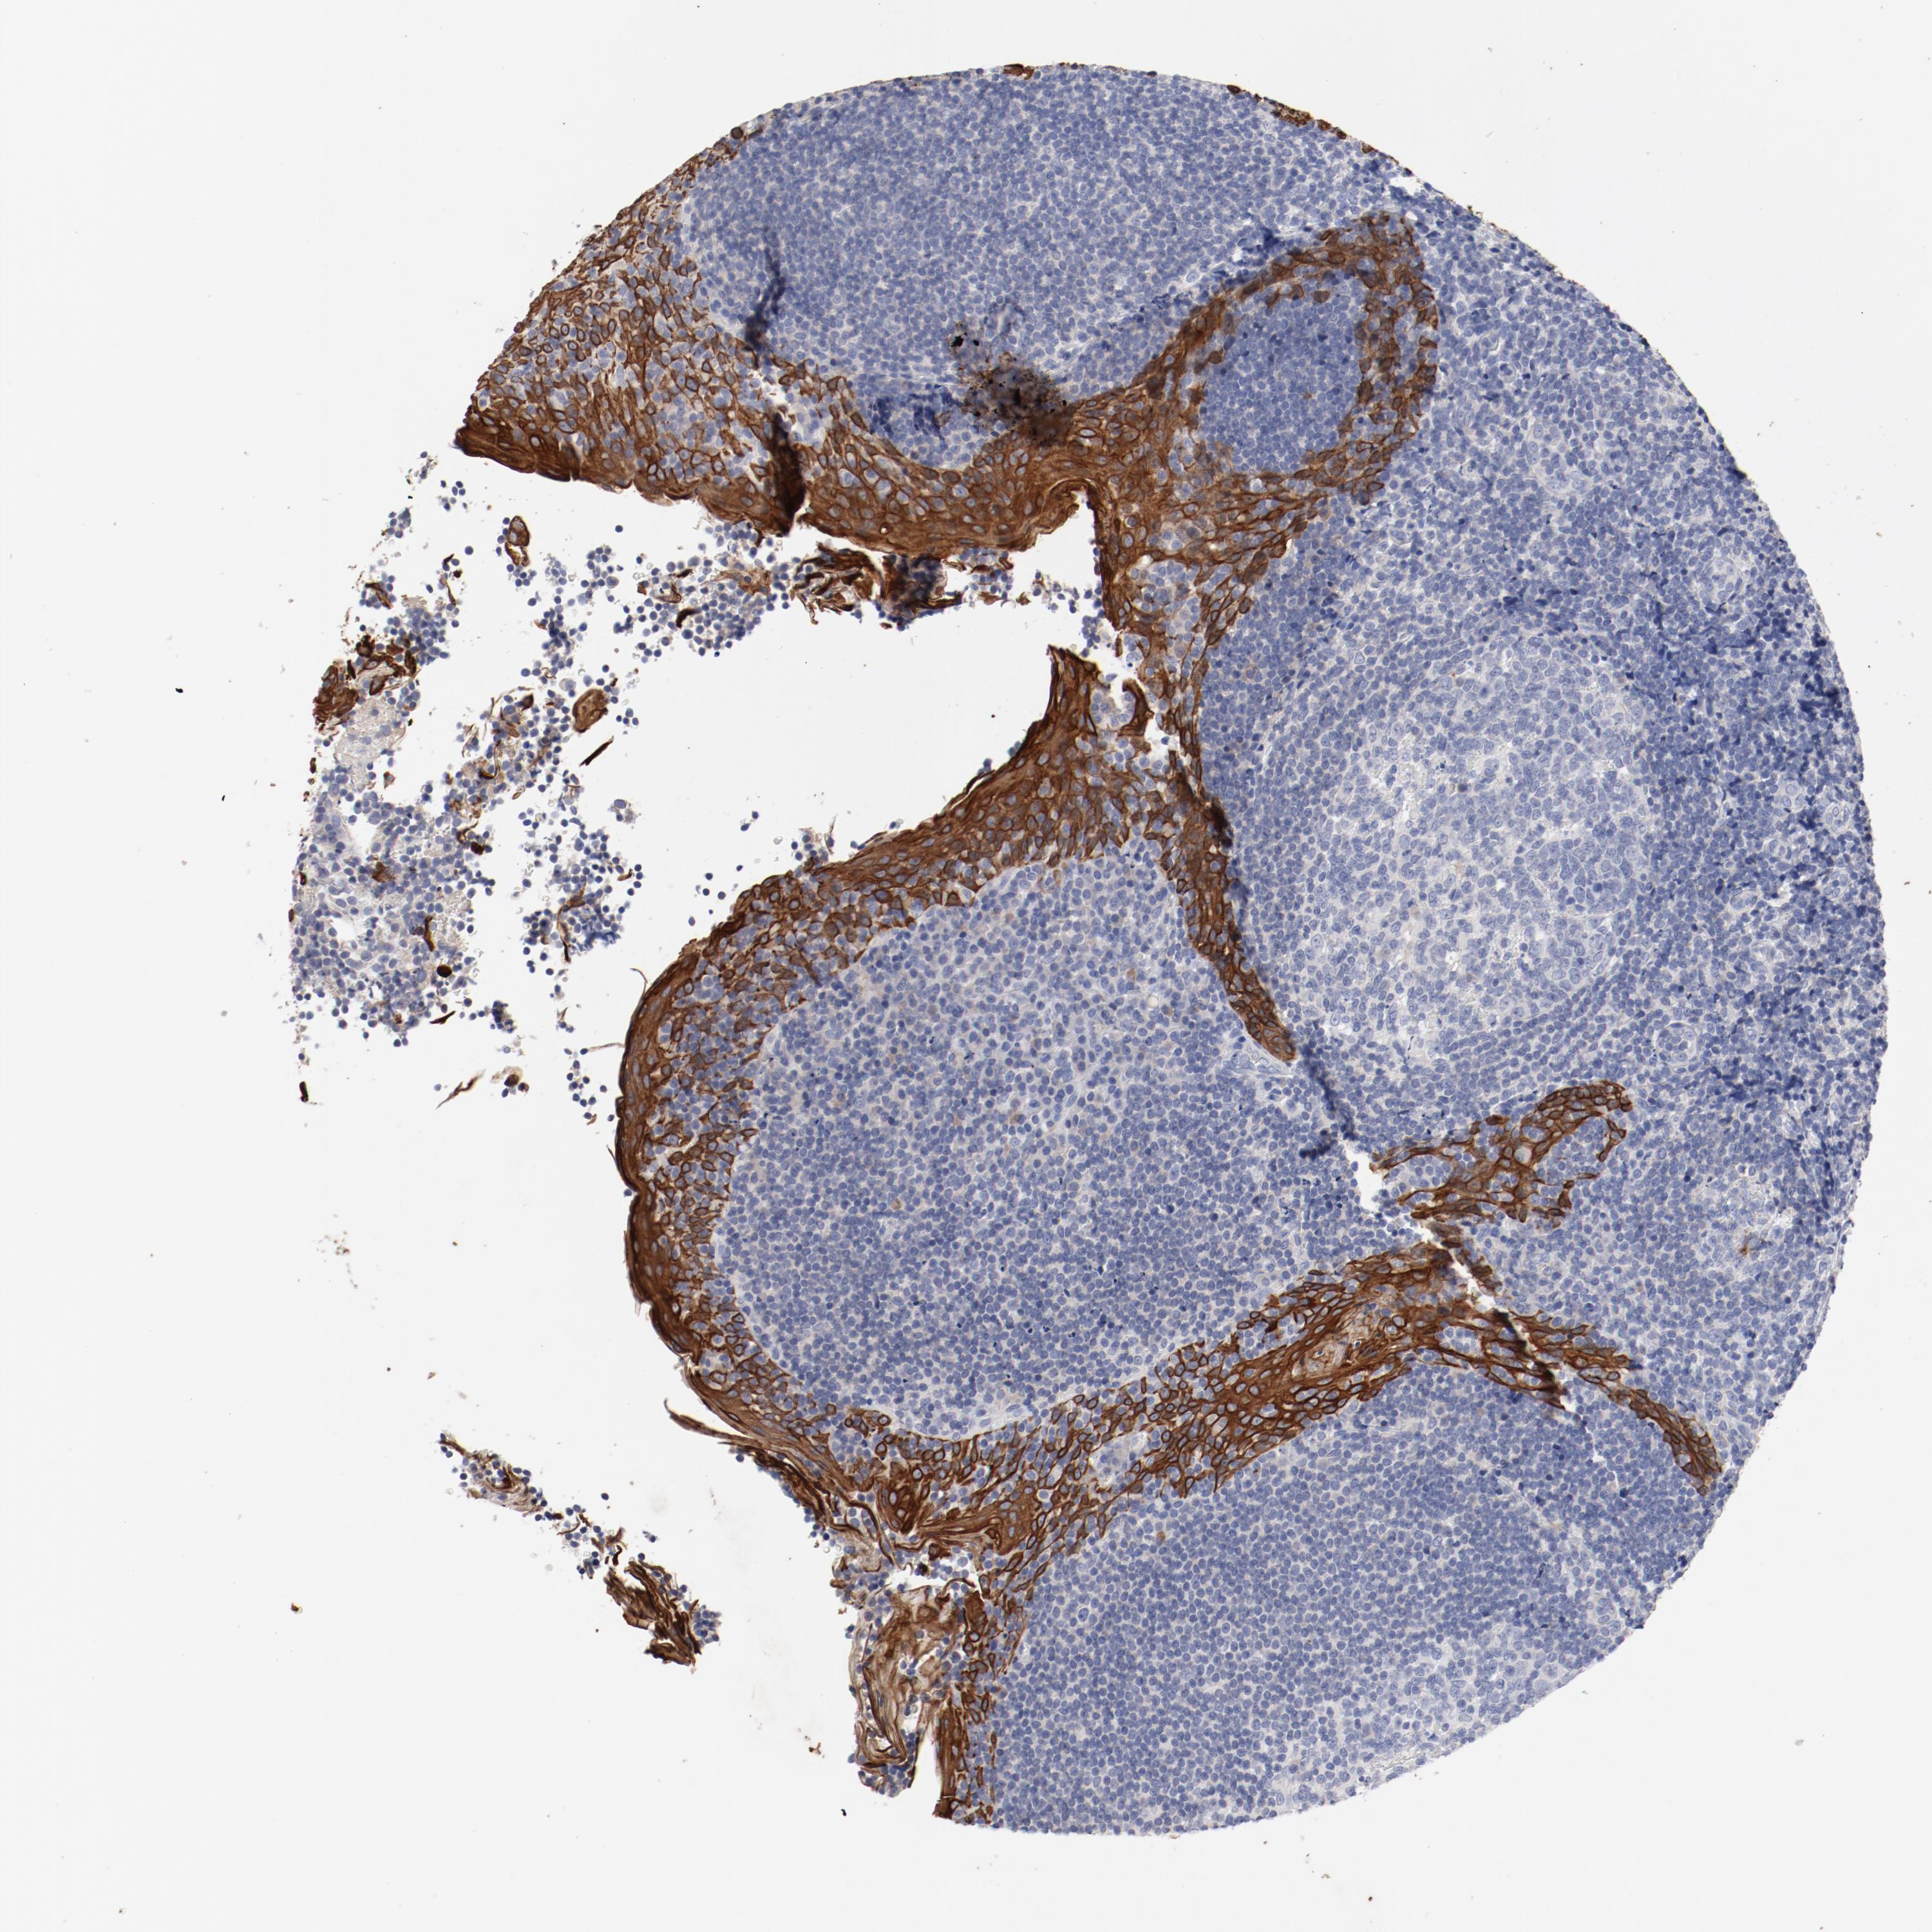

TSPAN6